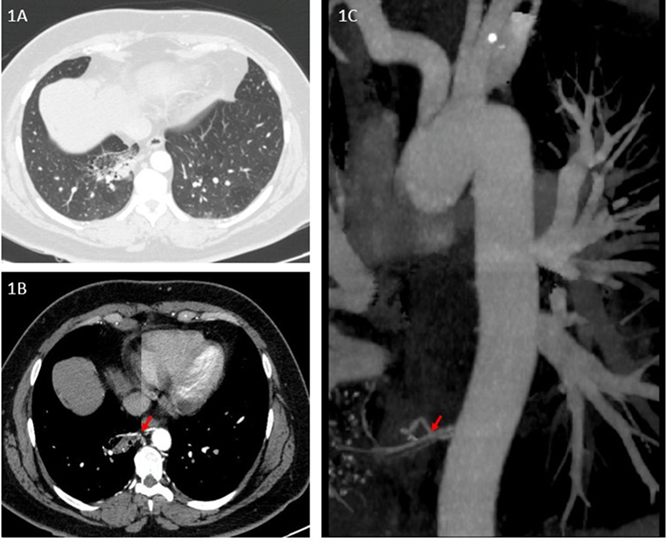

Estudios complementarios. Tomografías adicionales realizadas en hospitales de referencia nacional (enero–mayo 2024) confirmaron un área focal seudonodular en el lóbulo inferior derecho, asociada a un vaso sistémico aberrante proveniente de la aorta torácica (ver figuras 1A,1B,1C).

Figuras 1. Estudios complementarios

Figura 1ª. Angiotomografía de tórax muestra parénquima pulmonar del lóbulo inferior derecho con bronquiectasias quísticas. 1B. Ventana mediastinal muestra flecha roja señala arteria anómala que nutre secuestro pulmonar. 1C. En reconstrucción de aorta torácica y sus ramas, flecha roja marca el origen de la arteria anómala en la aorta torácica que confirma secuestro pulmonar.